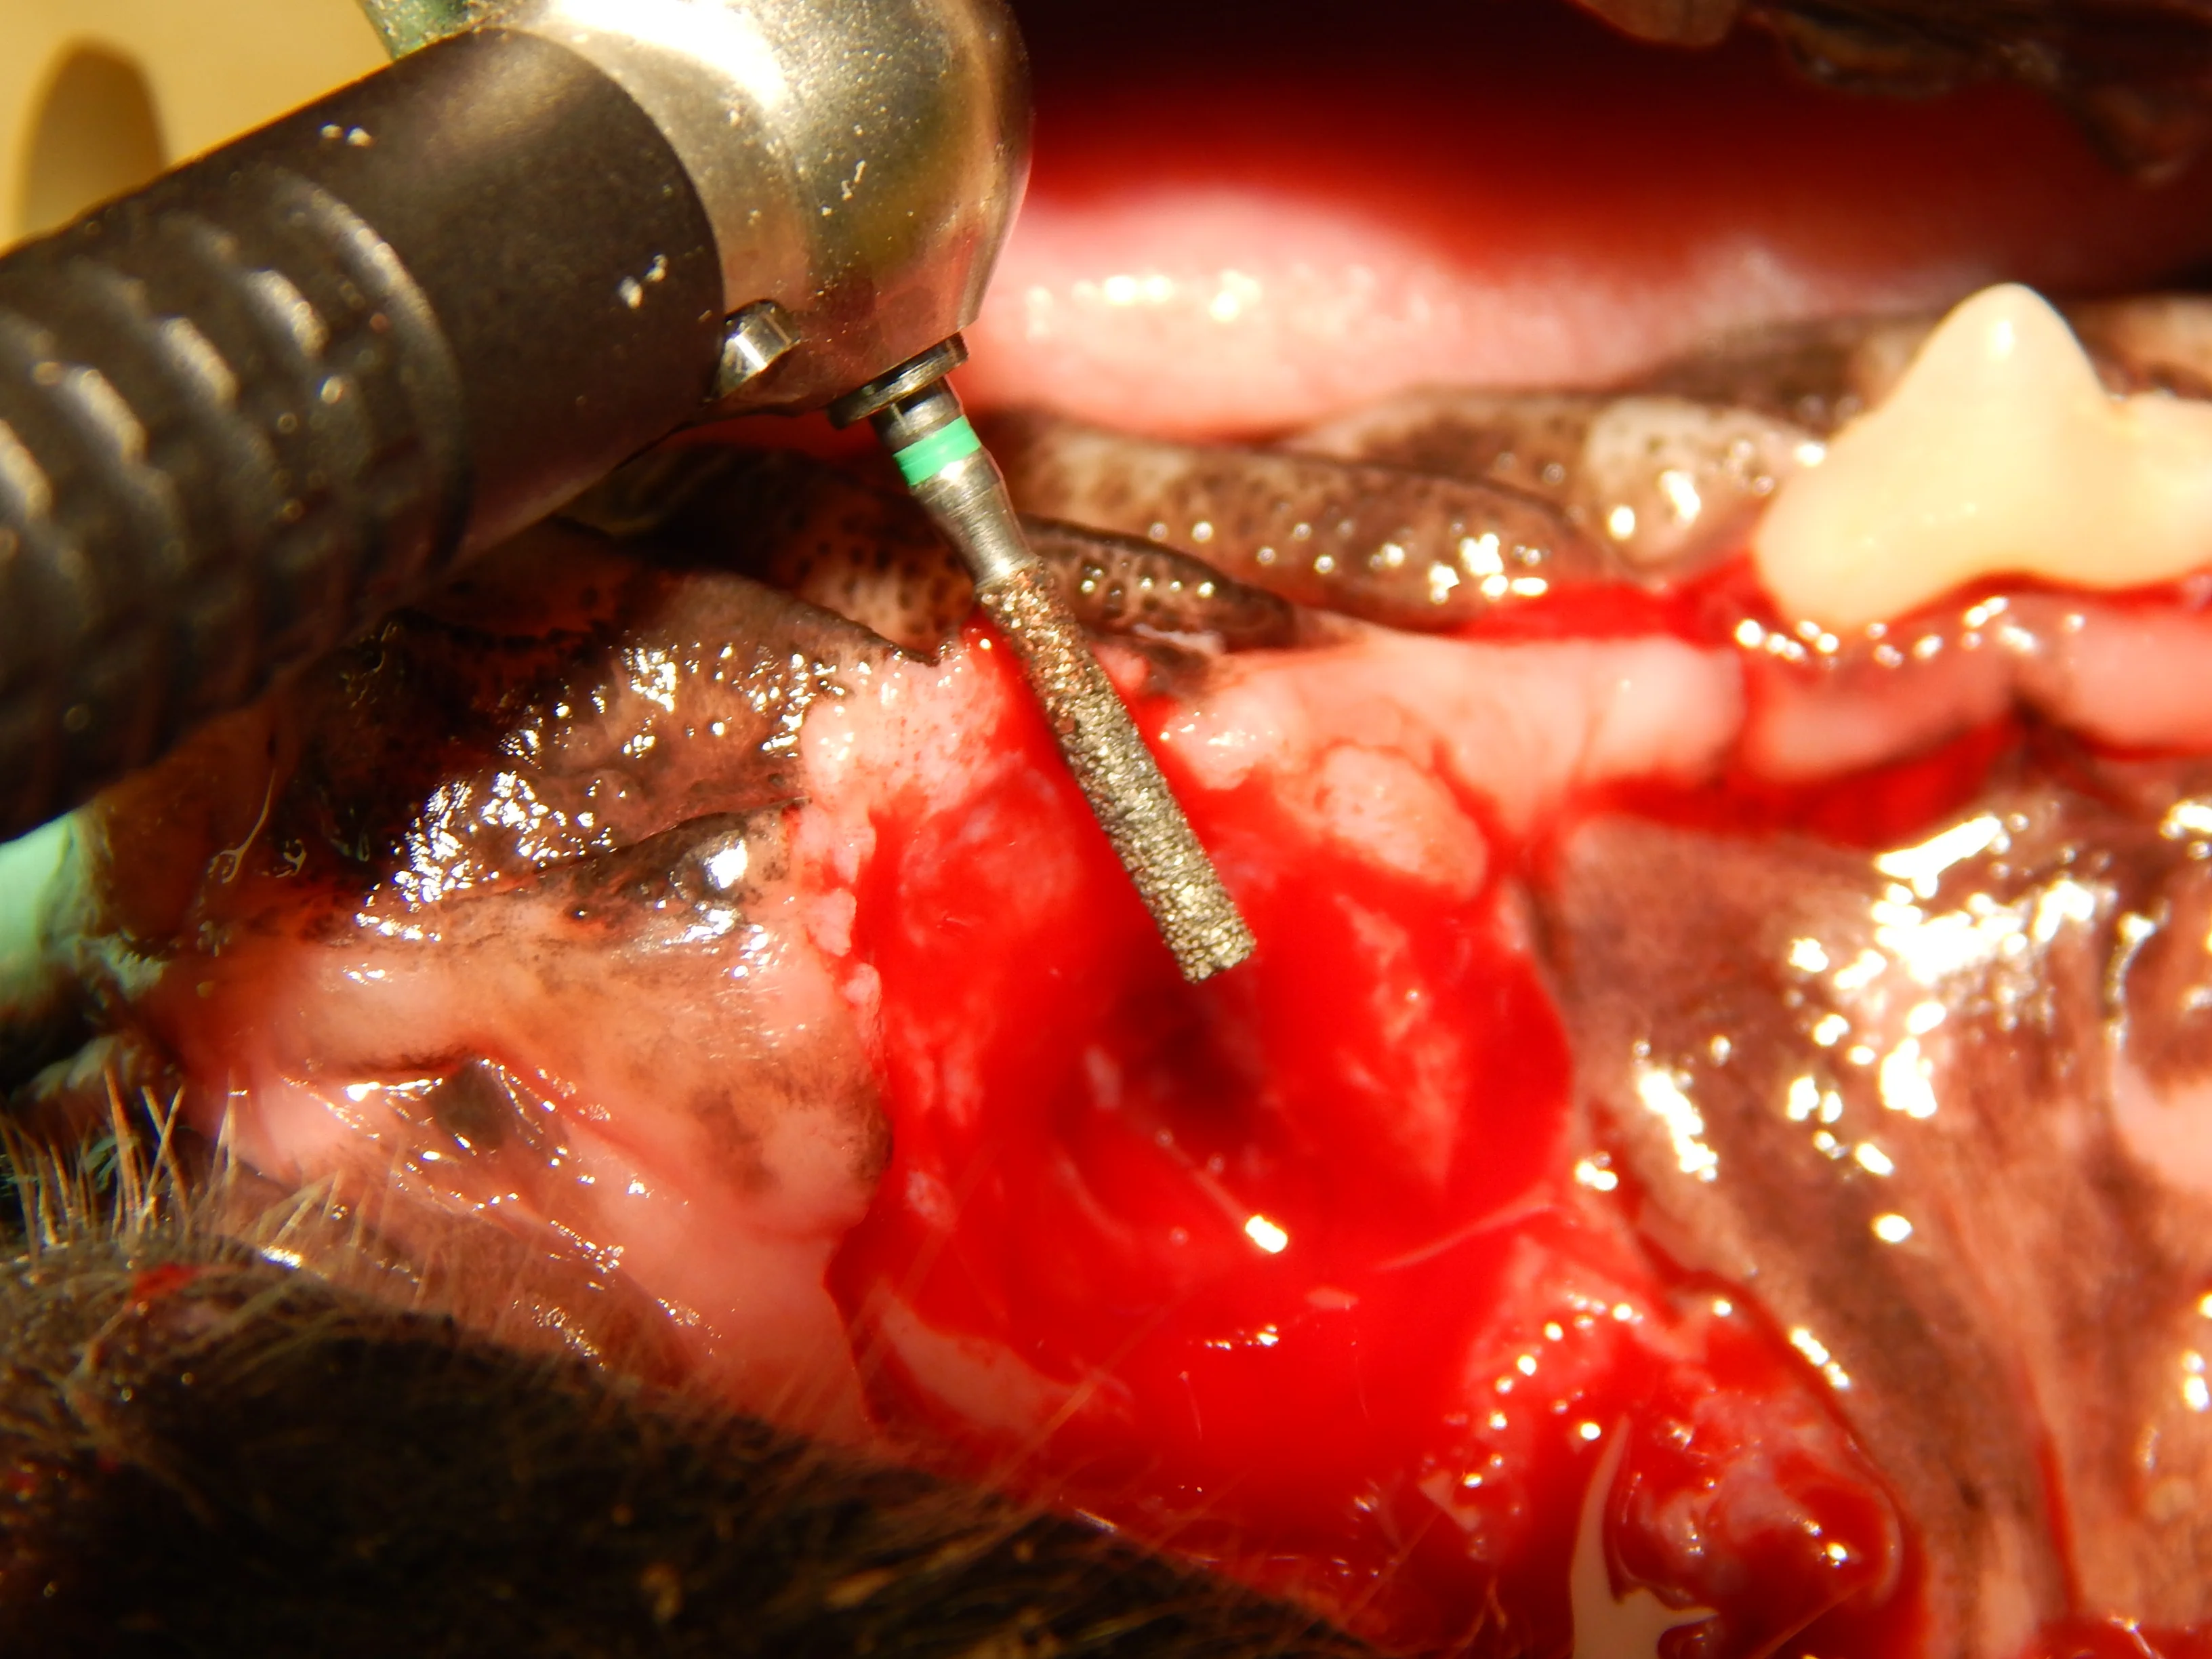

Oronasal fistulas may often be present prior to surgical extraction of maxillary teeth (Figures 6 and 7) but can also be a result of the surgical procedure. Although any maxillary tooth extraction can result in an oronasal fistula, it is most common following extraction of a maxillary canine tooth. Inadequate healing may lead to chronic oronasal fistulation (Figure 8). The quality of the tissue used to close the fistula and lack of wound tension are especially important in closure of oronasal fistulas. Development of a healthy recipient bed for the flap (Figure 9) and use of an Elizabethan collar to prevent self-trauma by the patient can also reduce flap failure.4

A coarse cylindrical diamond bur used to create a recipient bed (A). Removal of the epithelium allows improved healing of the sutured mucogingival flap (B).